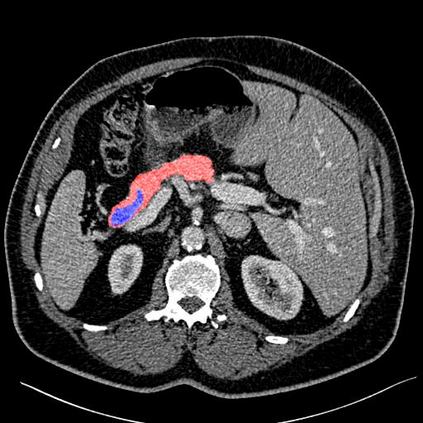

In this paper, we adopt 3D Convolutional Neural Networks to segment volumetric medical images. Although deep neural networks have been proven to be very effective on many 2D vision tasks, it is still challenging to apply them to 3D tasks due to the limited amount of annotated 3D data and limited computational resources. We propose a novel 3D-based coarse-to-fine framework to effectively and efficiently tackle these challenges. The proposed 3D-based framework outperforms the 2D counterpart to a large margin since it can leverage the rich spatial infor- mation along all three axes. We conduct experiments on two datasets which include healthy and pathological pancreases respectively, and achieve the current state-of-the-art in terms of Dice-S{\o}rensen Coefficient (DSC). On the NIH pancreas segmentation dataset, we outperform the previous best by an average of over 2%, and the worst case is improved by 7% to reach almost 70%, which indicates the reliability of our framework in clinical applications.